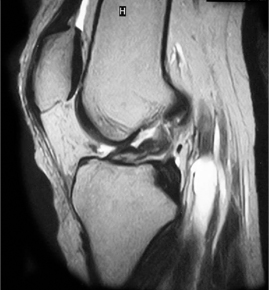

ACL 손상 방사선 사진3